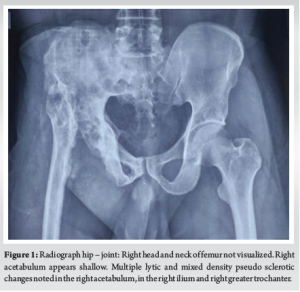

A 38- year- old male, presented with complaints of shortening of the right lower limb and limping for the past 20 years and pain in the right hip for 2 year. The patient had a history of trauma, 20 years back and was on native splinting for a period of 90 days. Following which, the patient complained of swelling and discharge from the right hip joint. He underwent wound exploration followed by drainage. Following which, the history is vague and non-contributory. He presented to the outpatient department of Sree Balaji Medical College and Hospital with pain in the right hip, which was insidious, throbbing type, associated with evening rise of temperature, along with a history of loss of weight and appetite for 2 mon. The patient had difficulty in performing daily activities. On physical examination, a swelling of 5 ×5 cm was identified along with local signs of infection / inflammation. X-ray imaging revealed sclerotic changes in the right acetabulum along with multiple lytic areas in the right ilium and right greater trochanter (Fig. 1).Computed tomography hip showed small cortical defects in right ilium with linear soft tissue calcified tract in the superior aspect of the right gluteal region (Fig. 2). Magnetic resonance imaging hip showed multiple pockets of fluid collections in the pelvis, along right iliacus and inguinoscrotal region, closely abutting the urinary bladder. Chest X-ray was normal. Laboratory investigations showed raised ESR-112 mm/hr, CRP-8.8mg/dL, total leucocyte count- 14,000/mm3, and differential count showed the predominance of neutrophils-81%, liver function tests showed elevation of gamma-glutamyl transferase and renal function tests were normal. Mantoux-negative, acid-fast bacillus-negative, pus culture and sensitivity showed no growth in culture. Gene X-pert Mycobacterium tuberculosis with rifampicin was not detected. An arthrotomy of the right hip was performed and the dissected material was sent to the histopathology lab for further evaluation. Grossly, the specimen received showed multiple gray-white to gray-brown soft tissue fragments altogether measuring-2×2 cm. Microscopically, sections showed spicules of necrotic bone, fibrocollagenous stroma, collections of foamy macrophages, and chronic inflammatory cell infiltrates composed of lymphocytes, plasma cells, and histiocytes (Figs. 3-5). Degenerated neutrophils, foreign body type of giant cells, and areas of necrosis are also seen. Thus, a HPE diagnosis of XO was signed out after carefully examining multiple sections in view of radiological changes not directly pointing toward a diagnosis of osteomyelitis. He was started on a course of antibiotics (linezolid), anti-inflammatory medications, calcium, and vitamin supplements for 1 month. The applied dressing was intact, sensations were present, and no distal neurovascular deficit was detected. He was advised an X-ray of the pelvis involving both hips anteroposterior view, after 1 week, after which patient contact was lost.

Xanthogranulomatous inflammation is a chronic inflammatory process, characterized by collections of foamy macrophages admixed with chronic inflammatory infiltrate. Delayed type hypersensitivity reaction of cell-mediated immunity has been implicated in the pathogenesis [2,3]. Xanthogranulomatous inflammation is seen involving organs such as gall bladder, kidney, colon, pancreas and salivary gland. Brain, lung, and bone are rarely affected (Borjan)[4]. very few cases of XO have been reported so far. When bone involvement ensues, the patient presents with both systemic and localized symptoms. It can present as a mass lesion extending into the surrounding tissue mimicking a tumor [5]. Our radiology revealed sclerotic and multiple lytic lesions noted in the right acetabulum, the right ilium, and the right greater trochanter. MRI in addition showed multiple pockets of fluid collection in the pelvis along the right iliacus and inguinoscrotal region closely abutting the urinary bladder, which is usually not associated in bone tumor. The earliest of these reports on XO were by Cozzutto and Carbone of the first rib and of the epiphysis of the tibia. In 1984, Cuzzoto identified and described it to be similar to Xanthogranulomatous lesions in the kidney and gallbladder characterized by foamy macrophages distributed in a mosaic pattern along with neutrophils, abundant plasma cells, and foam cells. Occasional foci of fibrin precipitates and multinucleated giant cells. The bacteriological assay carried out on the needle aspirate was negative in the first case [6]. In 2007, Vankalakunti et al. and colleagues reported ulnar XO in a post-menopausal woman. In this case, the patient had an increasing swelling on the extensor aspect of her right forearm for 2 years. The tissue culture was sterile, and XO was identified after a histopathologic examination [7]. There have been a few cases of XO mimicking a bone tumor, radiologically presenting as an osteolytic lesion along with the destruction of periosteum on X-ray. It may be associated with infection, obstruction, defective lipid transport, and immunological disturbances. The microscopic appearance of Xanthogranulomatous inflammation on histology shows characteristic clear and foamy cytoplasmic changes in the histiocytes along with plasma cell infiltration, multinucleated giant cells interspersed with lipid-laden macrophages, very rarely fibroblastic proliferation which imparts the characteristic yellow macroscopic appearance. This appearance, however, should be differentiated from a pseudoxanthomatous inflammation or malakoplakia characterized by Michaelis-Gutman bodies that stain positive with Von Kossa calcium and Prussian blue stains. Majority of XO cases, the patients undergo curettage of the involved bone along with bone grafting. To maintain the overall health of the patient antibiotics are started as a precautionary measure to maintain the surgical site wound. However, the exact role of antibiotics remains unclear, as XO is not always associated with active bacterial infection [8]. The histopathological differentials include lesions with foam cell collections – diagnosis for XO includes Langerhans cell histiocytosis, Erdheim-Chester disease, chronic recurrent multifocal osteomyelitis (chronic recurrent multifocal osteomyelitis) Xanthomas and some storage disorders with foam cell transformation, such as Gaucher’s and Nieman pick’s disease [9,10]. All these lack the inflammatory component seen in XO. In, Sinus histiocytosis with massive lymphadenopathy neutrophils are absent. It’s important to remember about the tumor with multiple lytic lesions metastatic clear cell adenocarcinoma from kidneys and other organs with clear cell components form challenges. IHC parameters are very useful in establishing the diagnosis.